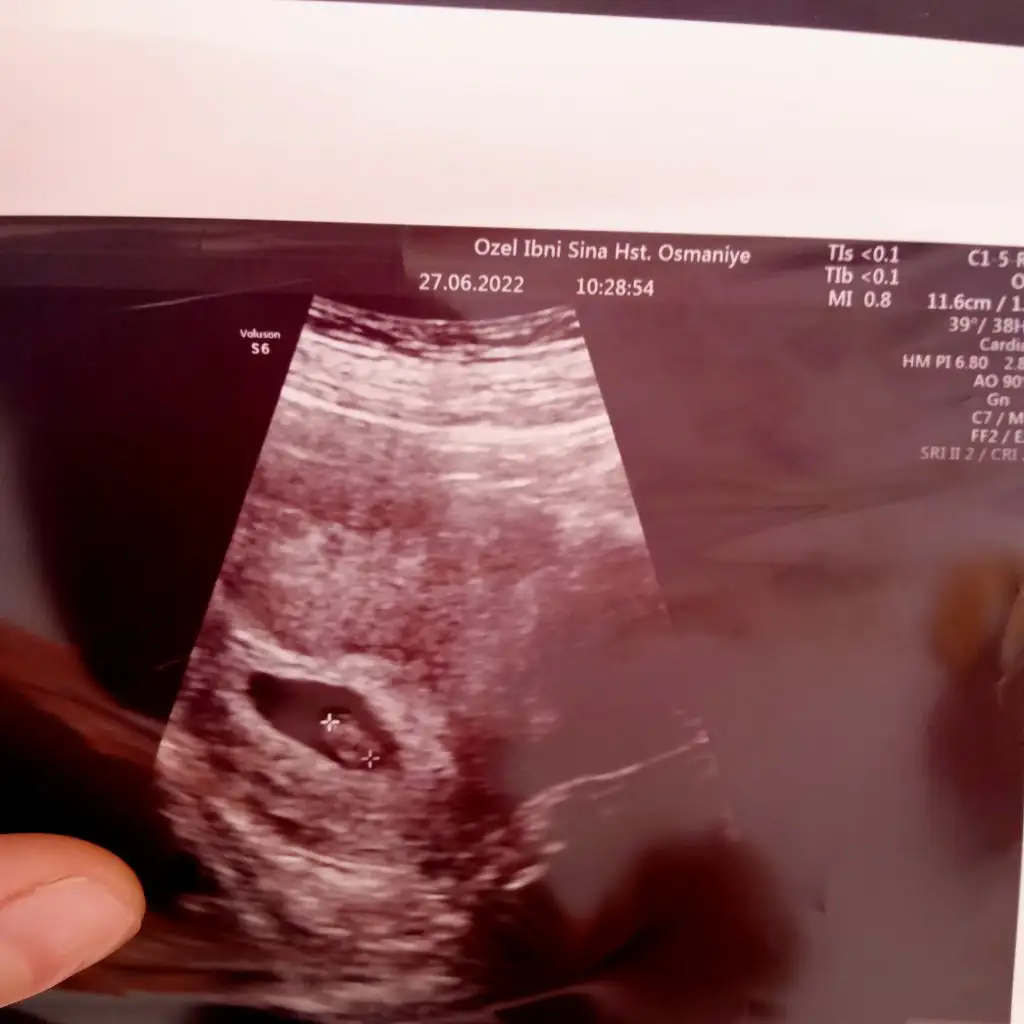

Bu da karın utrasyonu 7 haftapaşa gibi

Bilmm ikisinde de aynı taraftatuhafikisi fotoda da sağda, vajinal da sağda karından solda olması lazım

Birde böyle bakın ikisi yan yanatuhafikisi fotoda da sağda, vajinal da sağda karından solda olması lazım

tamam şimdi oldu siz fotoyu ters çekmişsiniz biri sağda biri solda, yaptığım tahmin geçerliBirde böyle bakın ikisi yan yana